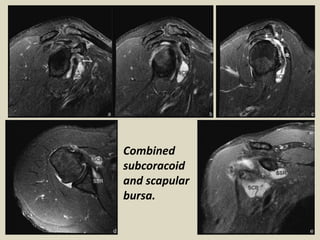

Arthrogram and shoulder MRI in combined bursa. Arthrogram

demonstrates pannus formation (arrow heads) in the axillary

recess. Contrast medium leakage into subacromial-subdeltoid bursa

(SASDB, white arrows) is noted, indicating a complete rotator cuff

tear. A faint contrast medium is present in the subcoracoid bursa

(SCB), which is confirmed on MRI and is believed to have originated

from SASDB. The fat-suppressed PDWI axial view shows the

communication (star) between the distended SCB and SASDB (white

arrows) with a relative clear fluid in the structures. The fat-

suppressed PDWI sagittal view shows conspicuous pannus

formation (arrowheads) within the glenohumeral joint (J) and

subscapularis recess (SSR) compared with the relative clear fluid

within SCB, which is circumstantial evidence for the lack of

communication between SCB and SSR and the glenohumeral joint.

Combined

subcoracoid

and scapular

bursa.